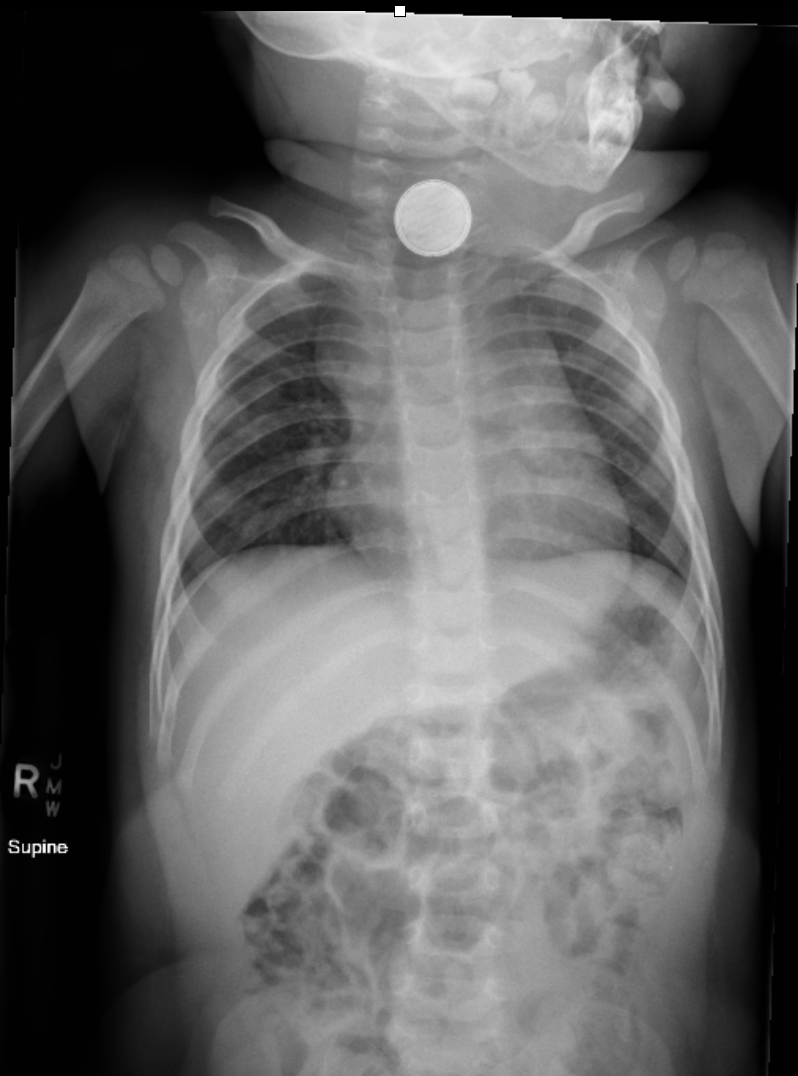

So you want an investigation like this (particularly if you’re a speaker looking to push things along…)

There are a few key things on the X-ray of course (I’m just going to go right ahead and assume you can spot the thing that is not supposed to be there):

- Location – there are classic points of particular concern because they represent points where a button battery might get stuck and can guide you as to which bits of the anatomy are at risk. The region of the clavicles corresponds with the cricopharyngeus, and a pretty high point in the airway. Head down a little lower to the vicinity of the carina and you’re in territory that’s also perilously close to the arch of the aorta. A bit lower and you’re getting to the pause point at the lower oesophageal sphincter.

- Identity – while you can’t always spot the nature of a foreign body, there is a chance you may be able to pick out the halo sign that is characteristic of a button battery. It’s the shadow created by the structure of the thing itself (unlike the homogenous disc of a coin as a comparator).

- Direction – this is a 3rd key item for a button battery. The damage created by a button battery occurs at the negative pole. The negative pole is the surface with less width on it. So the direction it is facing (best picked on a lateral) gives a pretty good clue as to where tissues are getting injured. For example if it’s around the carina or left main bronchus and the negative pole is facing to the patient’s spine, that big vessel is at risk. If it’s facing the sternum, the airways are in the firing line.